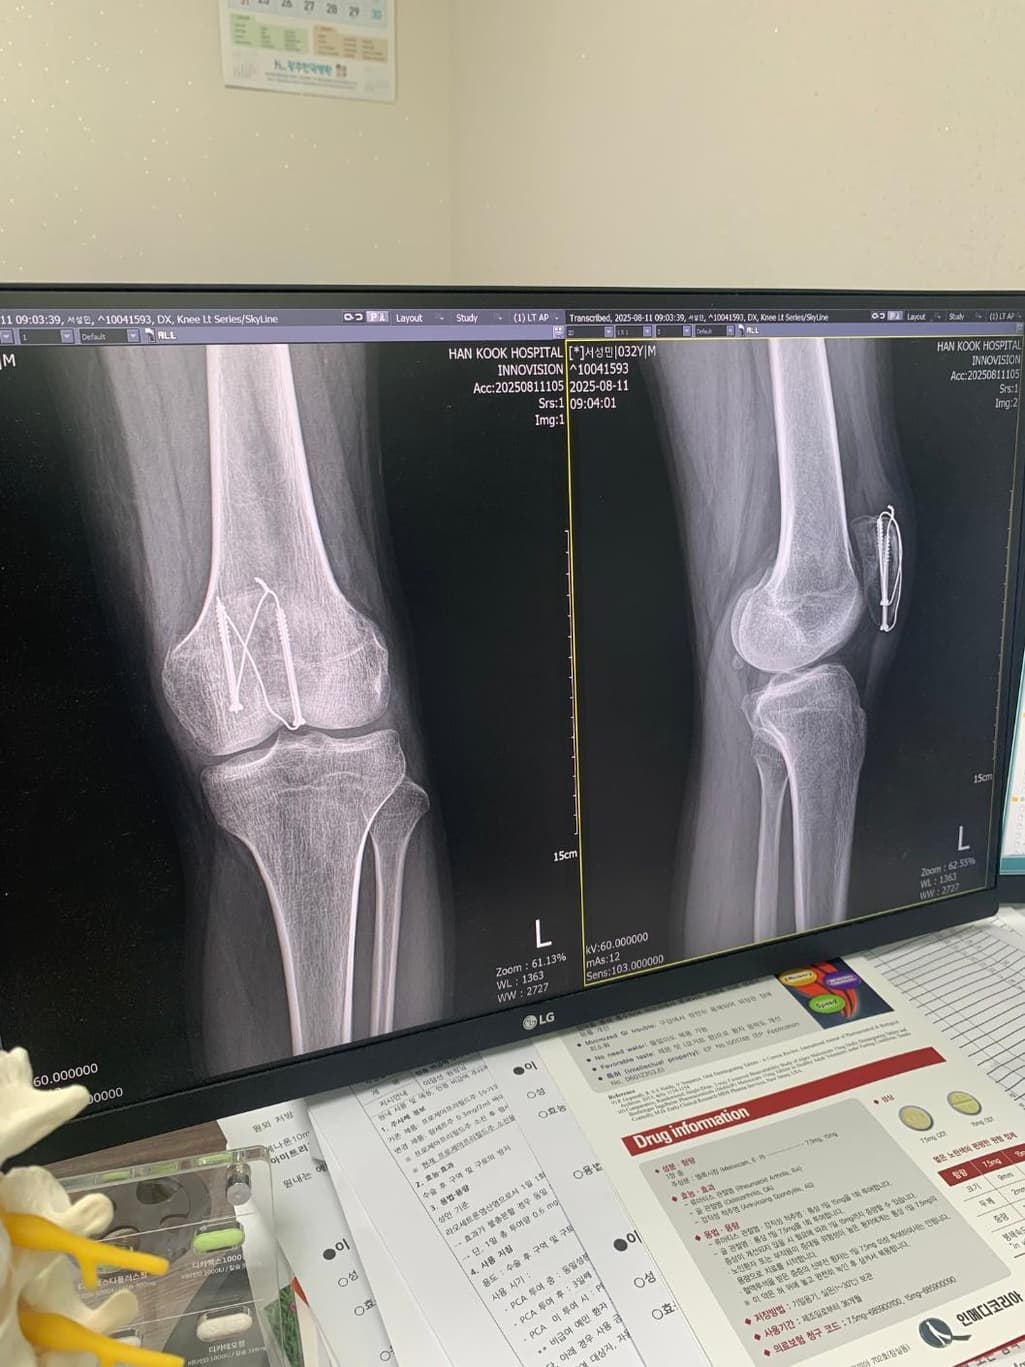

슬개골 골절 수술후 질문좀 드리겠습니다

슬개골골절 수술후 8주차 엑스레이입니다 질문좀드릴게여ㅠㅠ

1. 엑스레이상 유합이 잘되고있는건가요?

2. 수술부위를만져보면 한쪽부분이 골절선처럼 움푹파여서 보여지는데 혹시 뼈가 생기다가 만걸까요?

현재로썬 엑스레이상 유합이 잘되고있는것으로 보여지지만 다방면으로 확인이 필요한 부분이기에 전문의에 소견을 들어보시길 바랍니다.

보통 수술 후 봉합 부위에선 연부조직의 변화로 울퉁불퉁한 느낌이 들 수 있으며, 뼈가 생기다만것은 아니니 걱정하지않으셔도 됩니다.

엑스레이 상에서는 대체로 골절 부위가 붙어가는 양상이 보이는경우가 많으나 정확한 유합 여부는 담당 의사의 판독이 필요합니다.

수술 부위가 움푹 패여 만져지는 것은 뼈 모양이 완전히 매끄럽게 회복되지 않았거나 금속 고정물 주위 변화일 수 있습니다.

뼈가 생기다 만 것이라기 보다는 회복 과정에서 생긴 모양 차이일 가능성이 큽니다! 걱정된다면 다음 외래에서 촬영한 엑스레이와 촉진 소견을 함께 보여주고 확인하는 것이 가장 안전합니다!

사진상으로는 수술 이후 금속고정물이 자리를 잡고 골 유합이 이루어지고 있는 것으로 보이는데요, 통증이나 불편감이 심하지 않고 특별히 다른 소견이 없으셨다면 회복이 잘 진행되고 있는 것으로 생각됩니다.

표면의 변화는 뼈의 회복과정에서 일어날 수 있는 표면 변화로 생각됩니다.